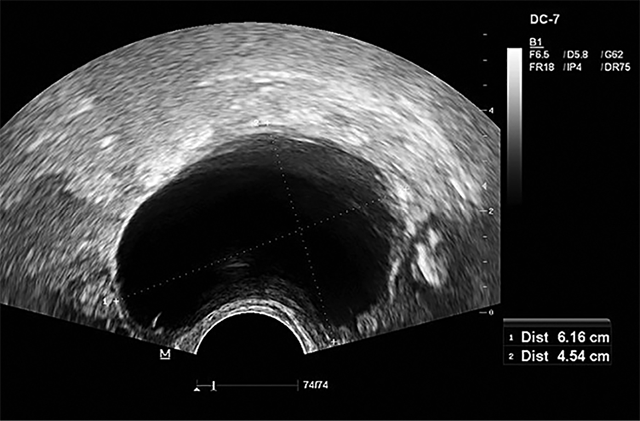

Apžiūrint per makštį – vulva ir makštis be matomų patologijų, makštyje – negausios šviesios išskyros, makšties gleivinė atrofiška, gimdos kaklelis epitelizuotas, uždaras, gimda ir gimdos priedai palpuojant neskausmingi. Transvaginalinio echoskopinio tyrimo duomenys: gimda retroversio padėtyje, 34x26 mm dydžio, gimdos dugne pastebėtas 8 mm dydžio kalcinuotas miomos mazgelis, gimdos gleivinė – 5 mm, homogeniška, dešiniosios kiaušidės projekcijoje nustatytas 6,2×4,5 cm dydžio cistinis darinys (žr. 2 pav.), užpildytas skaidriu turiniu, be kraujotakos, be intarpų, laisvo skysčio, papildomų darinių mažajame dubenyje nerasta. Atlikti kiaušidžių vėžio žymenys kraujyje: CA 125 (kU/l) 17,6 (norma <35 kU/L); HE4 (pmol/l) 71,2 (norma <140 pmol/l po menopauzės); ROMA indeksas (pomenopauzė) (%) 15,9 (rezultatas, lygus 12,5 % arba didesnis, reiškia aukštą epitelinio kiaušidžių vėžio riziką). Stebint pacientę nustatyta, kad cistinis darinys dešinėje kiaušidėje padidėjo nuo 2,7 cm iki 6,2 cm, todėl rekomenduotas operacinis gydymas – laparoskopinė abipusė salpingoovarektomija. Operacijos metu dešinėje kiaušidėje rastas apie 5‒6 cm dydžio cistinis darinys, kiti pilvo ir dubens ertmės organai – be pokyčių. Į pilvo ertmę suleista 50 ml sol. NaCl 0,9 proc., dalis jo išsiurbta ir išsiųsta citologiškai ištirti. Pašalinti abipusiai gimdos priklausiniai, jie atiduoti patologohistologiniam tyrimui atlikti. Remiantis patologohistologinio tyrimo duomenimis, kairėje kiaušidėje ‒ įterptinės cistos, kairiajame kiaušintakyje patologinių pakitimų nenustatyta. Dešinėje kiaušidėje ‒ įterptinės cistos, nustatytas dešiniojo kiaušintakio serozinis intraepitelinis pažeidimas (angl. serous tubal intraepithelial lesion; STIL) ir paratubarinė cista. Diagnozė šiuo atveju aprašoma kaip STIL – epitelio atipija, nepakankama STIC diagnozuoti. Mikroskopiniame aprašyme nurodyta, kad dešiniojo kiaušintakio fimbrijos epitelyje matyti zonų su epitelio ląstelių branduolių hiperchromija, polimorfizmu, persiklojimu, išnykusios epitelio blakstienėlės. Plonasienė cista išklota suplokštėjusiu epiteliu. Atlikus imunohistocheminį tyrimą, rastas stiprus (+++) p53 branduolinis dažymasis 100 % atipinių ląstelių ir stiprus (+++) Ki67 branduolinis dažymasis 1 % ląstelių. Atlikus operaciją, pacientei rekomenduota ambulatorinė gydytojo akušerio-ginekologo ir šeimos gydytojo priežiūra, paskirta planinė ginekologo konsultacija po 4‒6 mėn. endometriumui įvertinti, vartojant tamoksifeną. Praėjus 6 mėn., pacientė konsultuota gydytojo ginekologo. Patologinių pokyčių gimdoje, gimdos gleivinėje, dubens ir pilvo ertmės organuose nenustatyta.

2 pav. Cistinis darinys dešinėje kiaušidėje, TVE

Dešiniosios kiaušidės projekcijoje matyti 6,16×4,54 cm dydžio cistinis darinys, užpildytas skaidriu turiniu, be kraujotakos, be echopozityvių intarpų, pertvarų. Laisvo skysčio dubenyje nenustatyta.